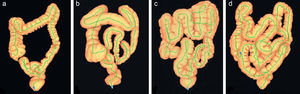

Fundamento para la utilización de dióxido de carbono durante la colonoscopiaComo se ha mencionado previamente, en todos los procedimientos de endoscopia digestiva se requiere la insuflación de gas, tradicionalmente aire ambiente, para lograr la distensión de la luz y conseguir la visualización de la mucosa. El volumen de gas insuflado excede en mucho el que existe en el tracto gastrointestinal en condiciones fisiológicas. De hecho, se estima que el gas fisiológico en el tubo digestivo es de 0,1 a 1,0 l8, mientras que el aire insuflado en el transcurso de una colonoscopia varía desde 8 a 14 l9,10. Esta variación en el volumen de aire insuflado puede explicarse entre otros factores por la longitud del colon que como bien queda reflejado en la figura 1 presenta importantes variaciones de unos individuos a otros, fundamentalmente a expensas en la variación de la longitud del colon sigmoide y del colon transverso11.

Diferencias anatómicas del colon mediante reconstrucción 3D con tomografía computarizada que muestra diversos grados de complejidad. (Fuente: Khashab et al.11)